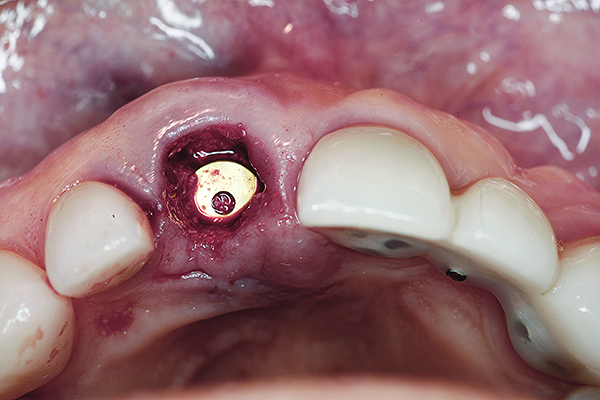

A 63-year-old female patient presented with mobility of her right maxillary incisor, tooth No. 8, secondary to endodontic therapy (Figure 1). Her medical and dental histories were non-contributory. Clinical and radiographic evaluations revealed an 8-mm probing depth on the palatal aspect. The tooth was deemed to be fractured (Figure 2). The treatment plan accepted by the patient was for extraction, immediate implant placement, and immediate provisional restoration, if possible.

Fig 1. Preoperative clinical photograph of fractured maxillary right central incisor (tooth No. 8).

Figure 1